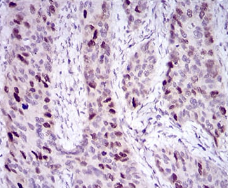

HDAC10 Mouse Monoclonal antibody[3B6B8]

IHC    1/200 - 1/1000